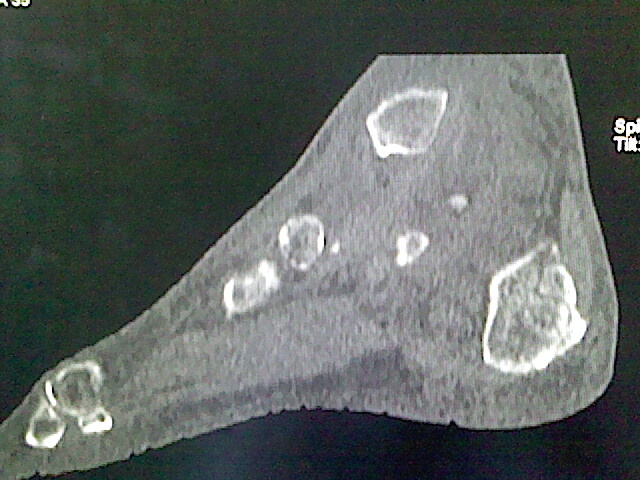

标题: CT16814:男,76岁,左小腿疼痛,不能站立 大家给看看 [打印本页]

男,76岁,左小腿疼痛,不能站立

本例骨质改变主要表现为滑膜或韧带区的骨侵蚀融解(胫腓联合区骨质破坏无硬化边),距骨后部骨质破坏区有硬化边及死骨样改变.所以,本例考虑关节结核可能性大,绒毛膜结节性滑膜炎多发于中年,且极少见于膝髋以外的关节,骨质硬坏也以压陷吸收为主,有明显的硬化边,骨膜增生呈结节状(可以mr鉴别),所以本例暂除外.

另不除外可引起相似表现的其他炎症如布氏杆菌性关节炎等